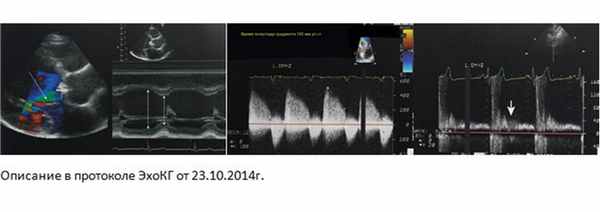

Результаты комплекснойтрансторакальной ЭхоКГ с допплеровским анализом от 23.10.2014., выявили следующие изменения: Аорта не утолщена, не расширена. Восх. отдел 3,3-3,4 см. ЛП не расширено 4,0 см. КДР=6,9 см; КСР=4,9 см; КДО 250 мл; КСО 138 мл. ФВ ЛЖ снижена 45-46% (biplaneSimpson). Зон нарушенной локальной сократимости нет. ТМЖП 1,0 см. ТЗСЛЖ 0,9 см. Аортальный клапан двустворчатый (1 тип). Амплитуда раскрытия нормальная. Кольцо АК 3,0 см. ПЗР 2,4 см. Легочная артерия не расширена. СДЛА 26 мм рт.ст. Признаков обструкции выходного тракта ЛЖ нет. Признаки недостаточности клапанов: митрального Iст., аортального IIIст., трикуспидальногоIст., легочного Iст.

Комментарий: мГДсТК=21 мм рт. ст., НПВ 2,4/1,1 см. АК v.contracta=0,75 см, время полуспада градиента давления на аортальном клапане =190-200 мс, мГДсАК=14 мм рт.ст. В нисходящей аорте регистрируется голодиастолический реверсивный поток с конечной скоростью 44 см/с.

Заключение: Врожденный порок сердца: двустворчатый аортальный клапан (Iтип). Недостаточность АК IIIстепени. Выраженная дилатация полости ЛЖ с умеренным снижением глобальной сократимости. Эксцентрическая гипертрофия миокарда ЛЖ.